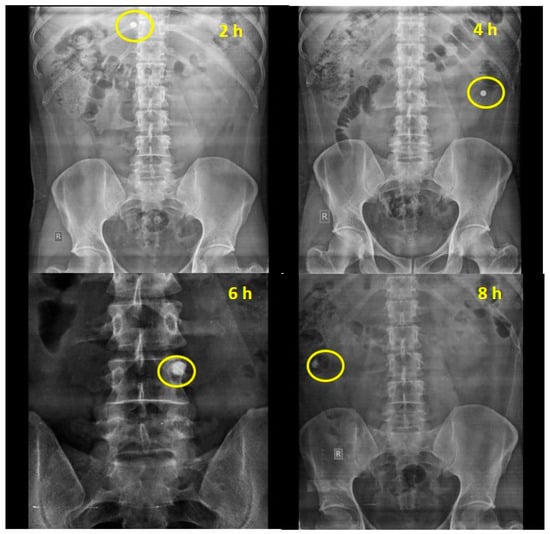

The results of the roentgenography study are represented for optimized chemically modified finger millet starch-coated mesalamine tablet. The roentgenographs of the rabbit with an empty stomach before administration of the tablet clearly showed the non-appearance of the tablet in the GIT of the test animal (Figure 2). The X-ray images of the tablets showed that the tablet maintained its integrity in the gastric environment. Interestingly, the transit of the formulation through the GIT was easily detectable. The roentgenographs of the tablets taken after 120 min showed that tablet reaches the small intestine in an intact form, revealing that the prepared formulations could be site specific (colon). No release of barium sulphate was observed in the small intestine, signifying that no drug was released in the small intestine. The time necessary to reach the colon was ~5–6 h [39]. Further, it has been found that the tablet reaches the colon after 360 min of administration and was slightly swollen. The findings of the study confirmed the in vitro drug release data. Further, the size of the starch tablet was increased after 480 min of administration, a better sign of drug release in the colon. The findings of the study showed good agreement with the study performed by [40]. Patel and Amin [40] concluded that a tablet coated with ethyl cellulose containing hydrophilic material; polyethylene glycol as an inner coating layer; and methyl acrylate, methyl methacrylate, and methacrylic acid copolymer (Eudragit® FS 30D) as outer coating layer remained intact until it reached the colon (5 h).

Figure 2. Roentgenography study of optimized phosphorylated mandua starch tablets in rabbits. Gastrointestinal transit of the colon-targeted tablets in rabbits: (a) 0 min, no tablet in the stomach; (b) 120 min, tablet approaching the small intestine; (c) 240 min, tablet approaching the small intestine; (d) 360 min, tablet reaches in the colon; and (e) 480 min, tablet in the colon.